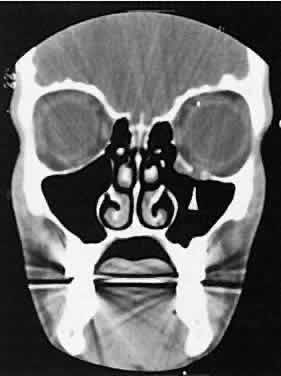

Lymphomatous involvement of the lacrimal gland resembles inflammatory dacryoadenitis radiographically. The enlarged lacrimal gland conforms to the shape of the globe, and the adjacent bone is normal (Fig. 18). We are aware of three high-grade lymphomas that affected the orbit and lacrimal gland and indented the globe, but this is distinctly unusual. Non-Hodgkin's B-cell lymphomas represent the most common type of lymphoma to affect the orbit. Literally any structure in the orbit can be subject to lymphomatous involvement; therefore, a lymphoma should be suspected in the presence of any amorphous isointense infiltrative process.

Fig. 18. Axial (A) and coronal (B) views of lacrimal gland lymphoma. There is homogenous enhancement of the enlarged lacrimal gland. Compared with Fig. 6, there is no difference.